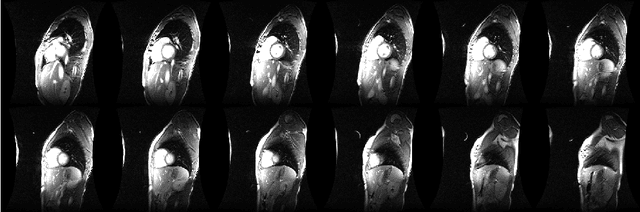

Abstract:It has been recently shown that incorporating priori knowledge significantly improves the performance of basic compressive sensing based approaches. We have managed to successfully exploit this idea for recovering a matrix as a summation of a Low-rank and a Sparse component from compressive measurements. When applied to the problem of construction of 4D Cardiac MR image sequences in real-time from highly under-sampled $k-$space data, our proposed method achieves superior reconstruction quality compared to the other state-of-the-art methods.